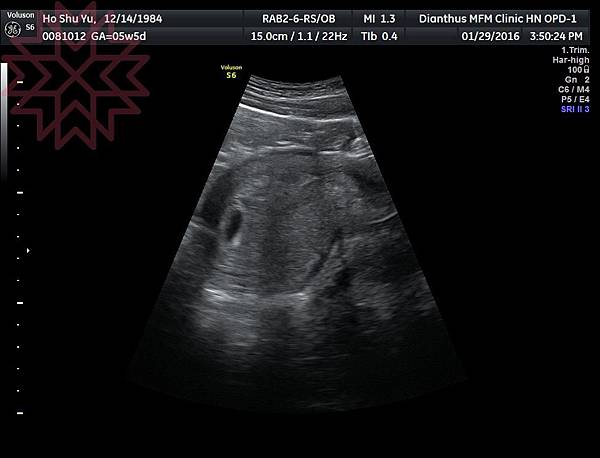

於是我在大約W6的時候,就到核心婦產科第一次看診,

這天看診的行程非常簡易,就是進行驗尿確認懷孕後,

再用超音波確認是不是子宮外孕!

這時候,孩子還是一顆黑豆般大小的點

開始擁有自己的房間

一切正常,醫生就跟我約兩週後廳胎兒心跳